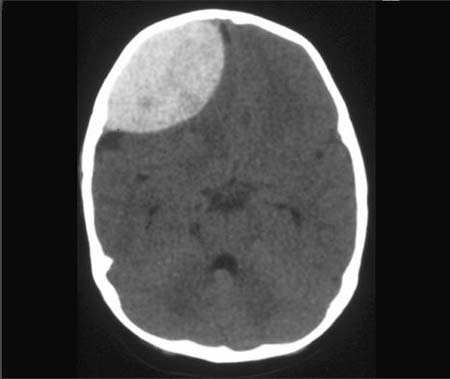

Acute Hemorrhage

… is actually a very serious situation.

I have been learning all about CT (computed tomography) Scans in school lately. Basically, they are just x-ray slices used to give clinicians a 3D image of the body part in question. For cases of serious trauma, they are the 1st imaging technique utilized because they visualize bleeds very well.

In an x-ray (and CT scan) areas that are WHITE are radiodense compared to the rest of the surrounding tissue:

So you can clearly see, there is a whole lot of blood in that frontal lobe. ouch.